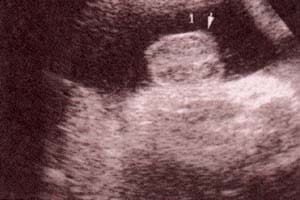

fig. 49. – (c). 30 semanas. labios. fig. 49. – (d). 38 semanas. labios mayores (1) nótese la hipertrofia del clítoris (2).